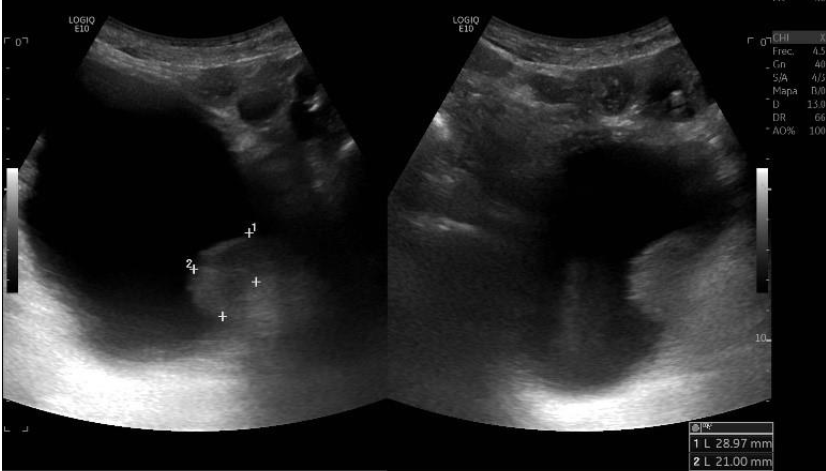

Ecoscopia clínica: izquierda, sonda cónvex en proyección transversal donde se objetiva la lesión en la pared lateral; derecha, proyección longitudinal donde se objetiva la misma lesión con una base pediculada.

Ecografía reglada: confirma lesión neoplásica con mismas características.

Lesión excrecente sésil sospechosa de malignidad. Juicio diagnóstico final hospitalario: carcinoma papilar urotelial vesical.

Diagnóstico diferencial: tumor vesical VS. impronta prostática VS. litiasis vesical VS. coágulo adherido VS. esquistosomiasis vesical.